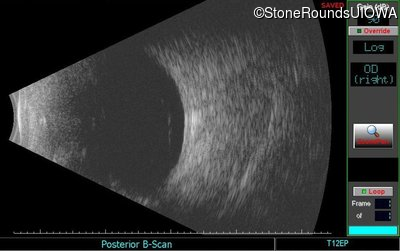

B-Scan Ultrasonography - Right - Light Perception

Exemplar